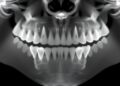

The evolution of stem cell research has ushered in a new frontier in developmental biology, particularly through the advent of stem cell-based embryo models (SCBEMs). These innovative constructs leverage the unique capabilities of pluripotent stem cells, enabling scientists to replicate the early stages of embryo development. By creating SCBEMs, researchers aim to glean insights into human development and the underlying mechanisms of various diseases, thereby paving the way for futuristic therapeutic advancements. However, the unfurling potential of SCBEMs brings forth a host of ethical and regulatory challenges, drawing mixed responses from governments and stakeholders across the globe.

An essential proposal arising from this analysis suggests that SCBEMs should be distinctly categorized apart from fertilized embryos. By doing so, researchers can sidestep some of the stringent limitations placed on embryo research while establishing clear ethical guidelines that consider the unique characteristics of SCBEMs. This differentiation can provide researchers with the necessary latitude to explore innovative research avenues while maintaining a responsible ethical standpoint.